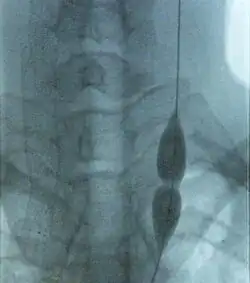

Balloon angioplasty and stenting have been proposed as treatment options for CCSVI in MS. The proposed treatment has been termed "liberation therapy" though the name has been criticized for suggesting unrealistic results.[14]

Balloon angioplasty in a preliminary, uncontrolled, unblinded study by Zamboni improved symptoms in MS in a minority of treated people.[44] Although the procedure pushes the vein open temporarily, the effect does not persist,[22] supporters advise against using stents.[45]